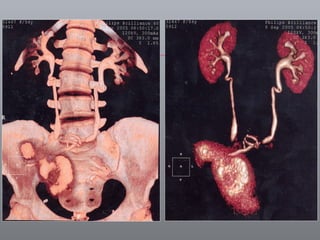

Câncer de Bexiga Estudos de imagens Diagnóstico Ultrassonografia Urografia excretora Estadiamento CT RNM Rx tórax  Cistoscopia + biópsia + biópsias randomizadas

CT